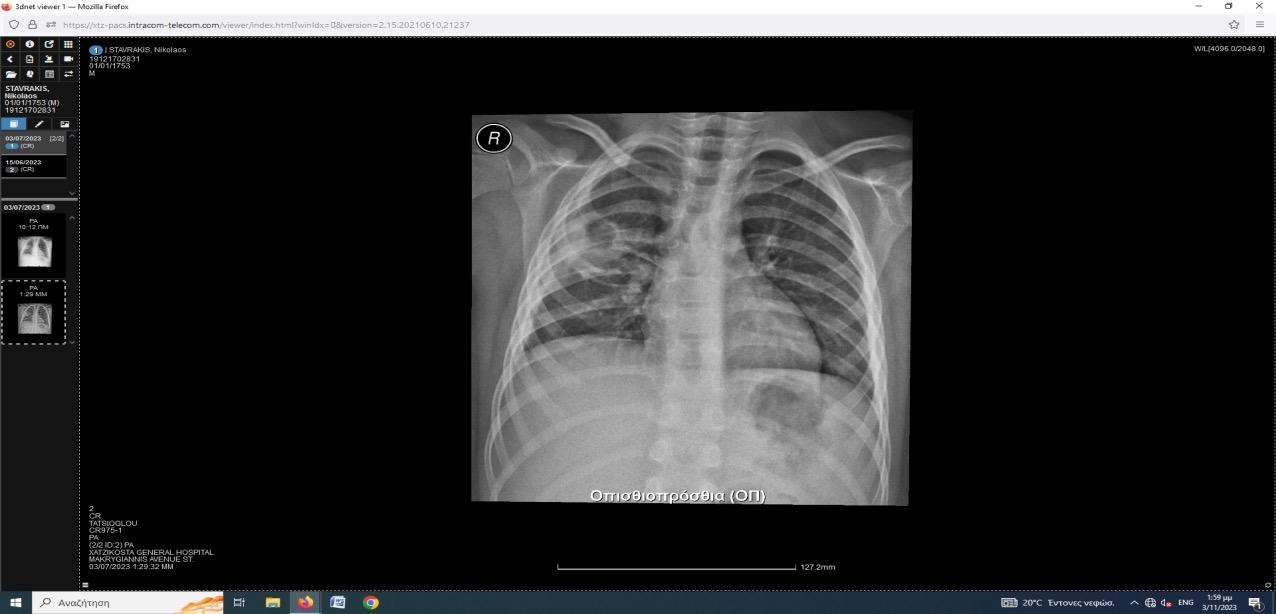

Επιπλεγμένη πνευμονιοκοκκική πνευμονία από ορότυπο 3 σε εμβολιασμένο ανοσοεπαρκή παιδιατρικό ασθενή.

Μαργαρίτα-Ευθαλία Παπασάββα, Δήμητρα Σαββίδου, Τζωρτζίνα Τζανακάκη, Ανδρέας Ηλιάδης, Βασιλική Γκέτση